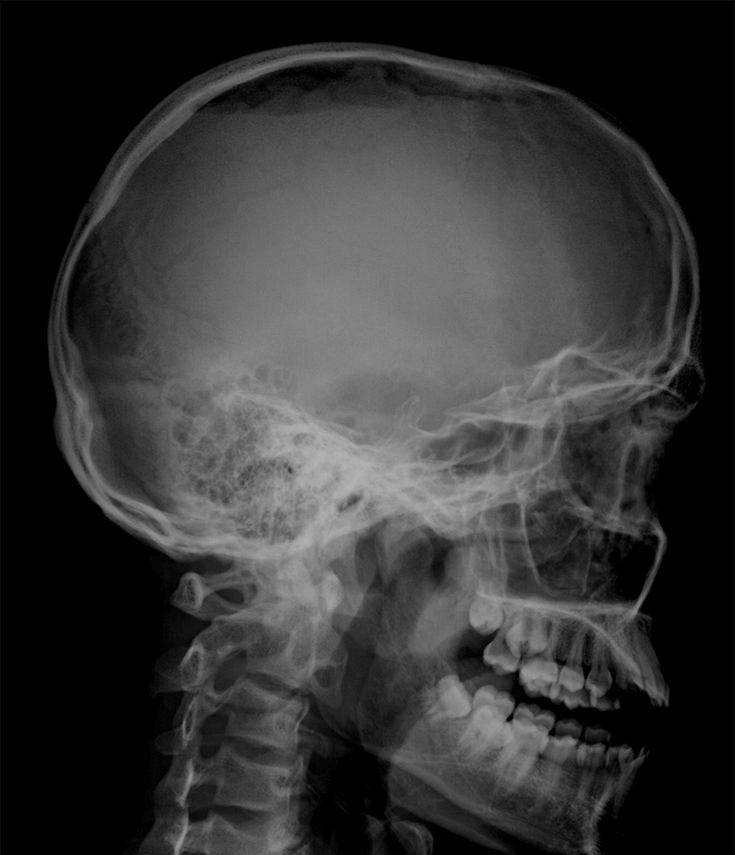

Рентгенография черепа и позвоночника: изображение и диагностика